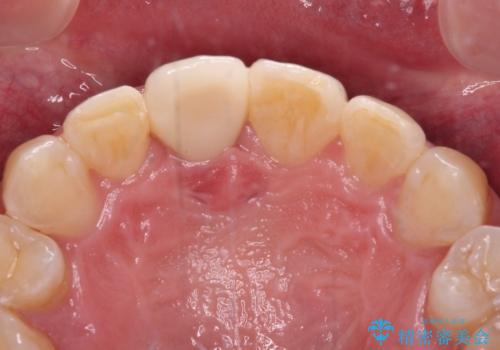

- ぶつけて前歯が折れてしまったとのことで来院された患者様です。

折れてしまった前歯は軽傷であり、歯内の歯髄に影響は及んでいませんでした。

通常では速やかにオールセラミッククラウンにて補綴治療を行うのですが、デコボコしている歯列も気になっていたため、事前に矯正治療を行うこととしました。

上顎歯列の叢生が著しかったため、上顎左右第一小臼歯2本を抜歯し、目立たないワイヤー装置にて治療を進めることとしました。

矯正治療後にはオーダーメイドタイプのオールセラミッククラウンを装着し、自然な口元に仕上がりました。